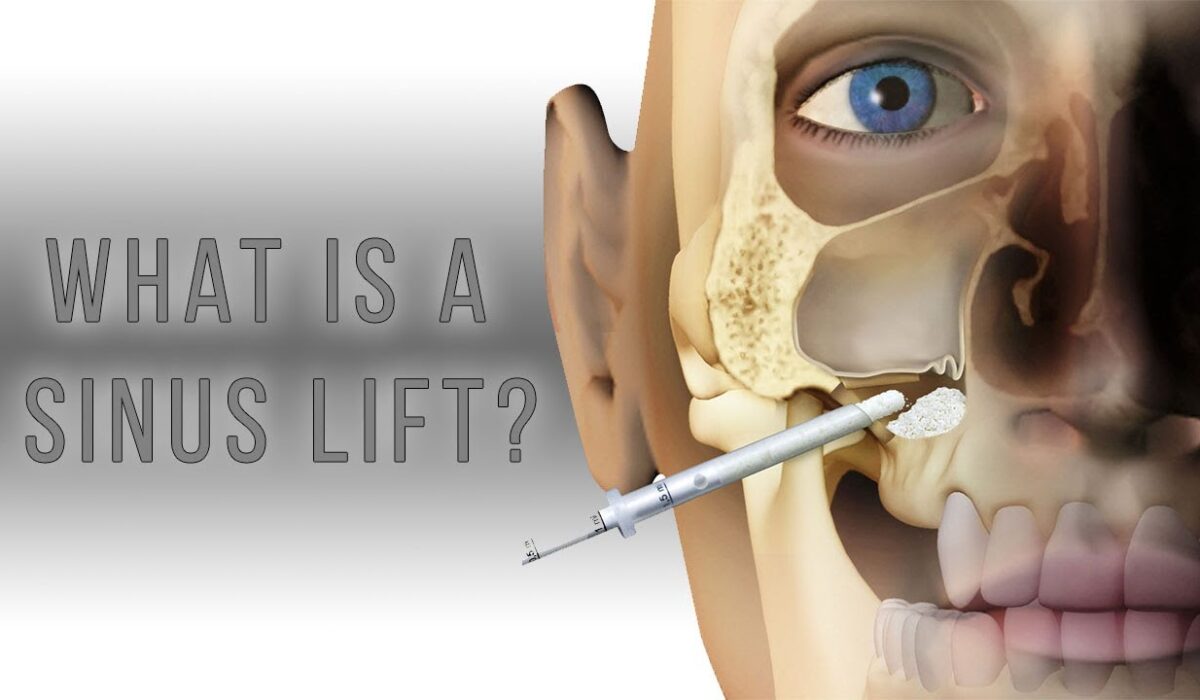

Η ανύψωση ιγμορείου είναι μια εξειδικευμένη οδοντιατρική επέμβαση που εφαρμόζεται όταν χρειάζεται να τοποθετηθούν οδοντικά εμφυτεύματα στην άνω γνάθο, αλλά δεν υπάρχει επαρκές οστό για την υποστήριξή τους. Αυτό συμβαίνει συχνά στην οπίσθια περιοχή της άνω γνάθου (στην περιοχή των γομφίων και των προγομφίων), όπου τα ιγμόρεια βρίσκονται κοντά στις ρίζες των δοντιών.

Τι είναι η Ανύψωση Ιγμορείου;

Η ανύψωση ιγμορείου, γνωστή και ως Sinuslift, είναι μια χειρουργική διαδικασία που επιτρέπει την αύξηση του ύψους του οστού στην άνω γνάθο με την τοποθέτηση οστικού μοσχεύματος. Το οστικό μόσχευμα τοποθετείται κάτω από το ιγμόρειο, το οποίο “ανυψώνεται” για να δημιουργηθεί χώρος για τα εμφυτεύματα. Αυτή η διαδικασία είναι απαραίτητη όταν το υπάρχον οστό δεν είναι αρκετό για να υποστηρίξει τα εμφυτεύματα, είτε λόγω απώλειας δοντιών για μεγάλο χρονικό διάστημα είτε λόγω της φυσιολογίας του ασθενούς.

Υπάρχουν δύο βασικές τεχνικές ανύψωσης ιγμορείου, και η επιλογή εξαρτάται από το μέγεθος του οστικού ελλείμματος και τις ανάγκες του ασθενούς:

Κλειστή Τεχνική Ανύψωσης Ιγμορείου (Closed Sinus Lift):

- Η κλειστή τεχνική ανύψωσης ιγμορείου είναι λιγότερο επεμβατική και χρησιμοποιείται όταν χρειάζεται μόνο μια μικρή ανύψωση του ιγμορείου (μέχρι 3-4 χιλιοστά).

- Η διαδικασία γίνεται μέσα από την οπή του εμφυτεύματος, και η ανύψωση γίνεται σταδιακά με ειδικά εργαλεία που μετακινούν την μεμβράνη του ιγμορείου προς τα πάνω.

- Η μέθοδος αυτή είναι γρήγορη και μπορεί να συνδυαστεί με την άμεση τοποθέτηση του εμφυτεύματος.

Ανοικτή Τεχνική Ανύψωσης Ιγμορείου (Open Sinus Lift):

- Η ανοικτή τεχνική χρησιμοποιείται όταν το οστικό έλλειμμα είναι μεγαλύτερο και απαιτείται σημαντική ανύψωση του ιγμορείου (άνω των 4 χιλιοστών).

- Κατά τη διάρκεια της διαδικασίας, γίνεται μια τομή στα ούλα για να δημιουργηθεί πρόσβαση στο ιγμόρειο, και η μεμβράνη του ιγμορείου ανυψώνεται με προσοχή.

- Στη συνέχεια, τοποθετείται οστικό μόσχευμα στην περιοχή, το οποίο θα βοηθήσει στην αύξηση του οστικού όγκου. Το μόσχευμα μπορεί να προέρχεται από τον ίδιο τον ασθενή, από δοτές, ή να είναι συνθετικό.

- Ανάλογα με την περίπτωση, η τοποθέτηση των εμφυτευμάτων μπορεί να γίνει είτε ταυτόχρονα με την ανύψωση του ιγμορείου είτε μετά από μερικούς μήνες, όταν το οστό έχει ενσωματωθεί πλήρως.